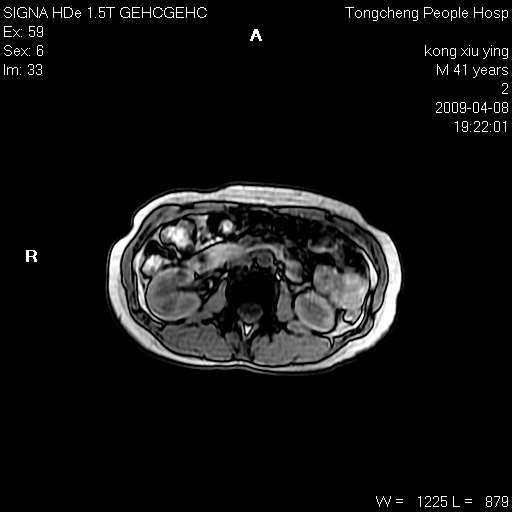

标题: CL1008:【经典】胆囊石榴籽样结石。 [打印本页]

标题: CL1008:【经典】胆囊石榴籽样结石。

女,41岁。健康体检——彩超提示:胆囊显示不清。平素健康,无不适感。

腹部mr扫描及mrcp,图像如下:

胆囊石榴籽样结石。